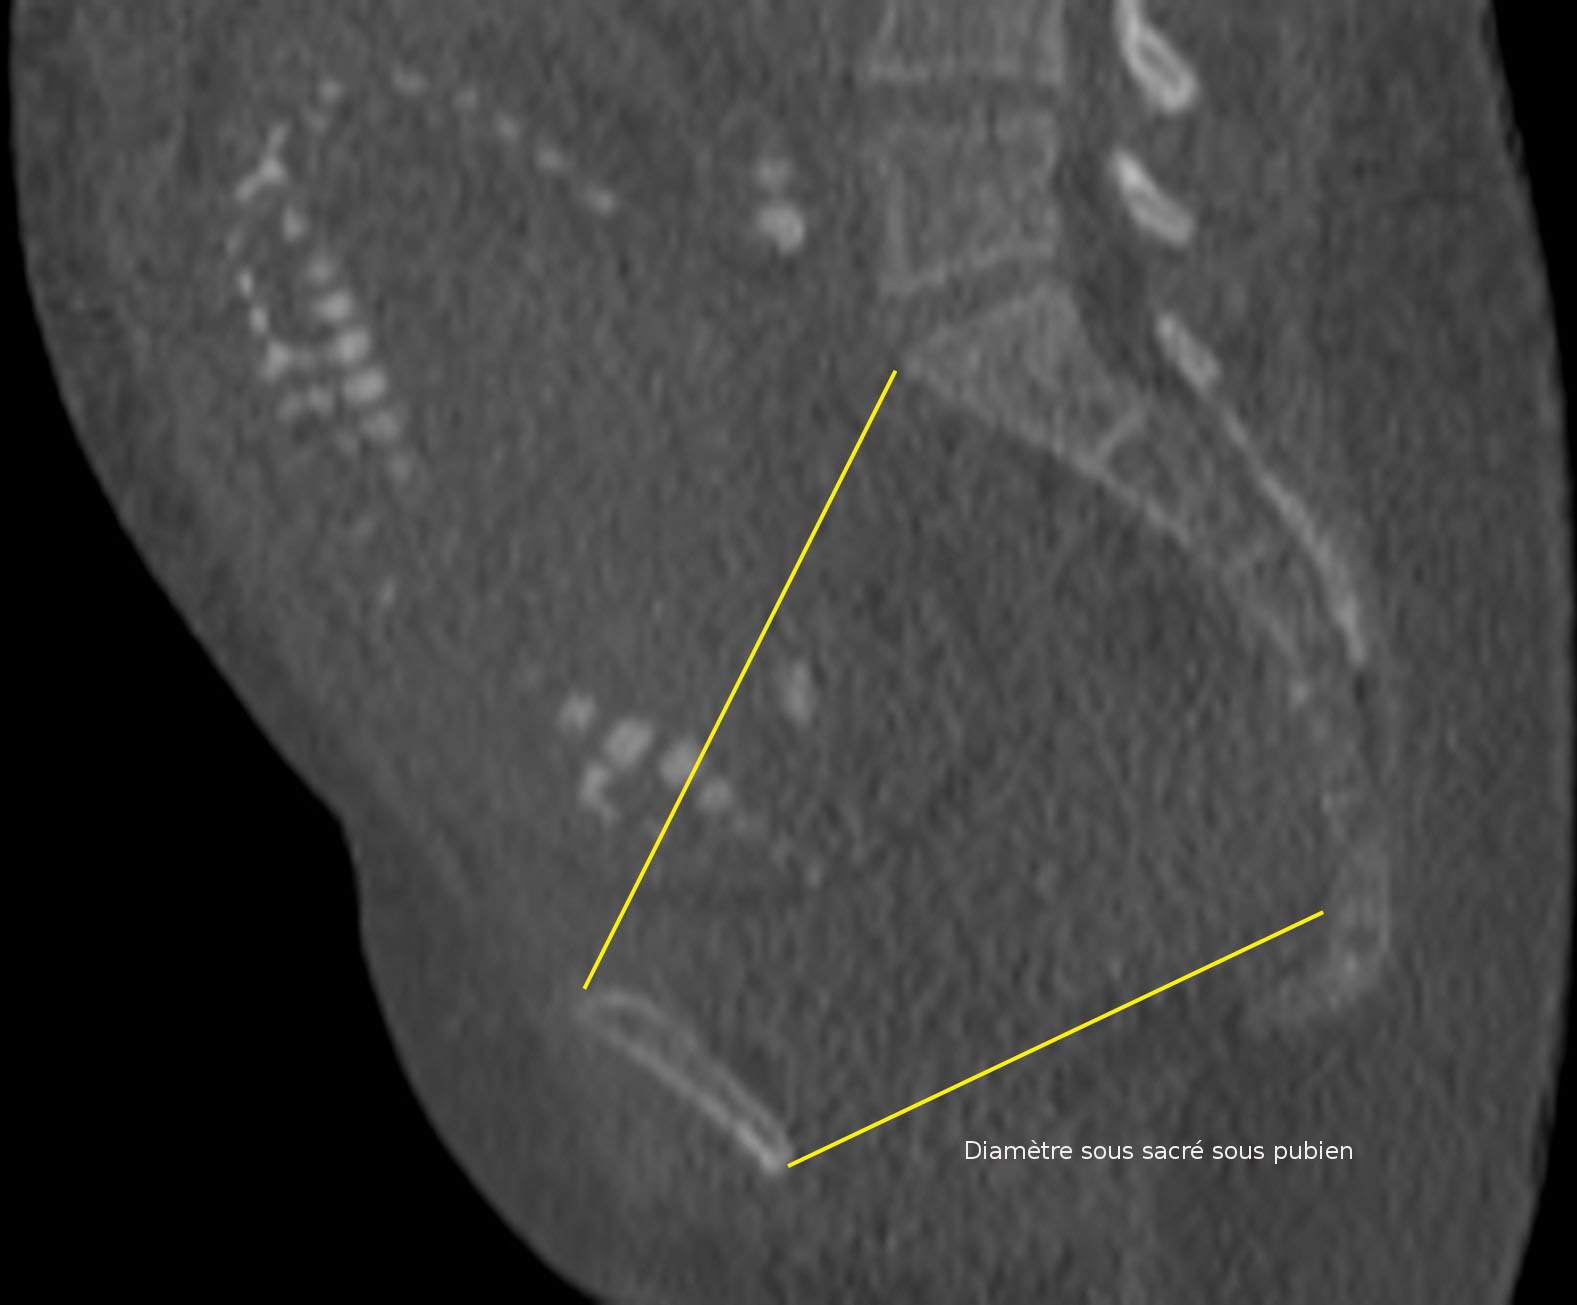

Les coupes sont également travaillées en mode rendu volumique. Il est ainsi possible d'obtenir très facilement les images pour l'étude morphologique du bassin.

Le foetus peut être facilement « effacé » afin de ne pas gêner l'étude anatomique du bassin maternel Il est aussi possible de mesurer les différents diamètres utiles sur ces reconstructions volumiques.

Grâce aux reconstructions en rendu volumique, il est possible d'apprécier ainsi facilement la morphologie du bassin, en particulier du détroit supérieur.